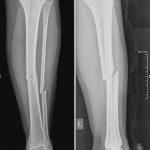

Այս ուսումնասիրությունը հիմնված է 21 հիվանդների (17 տղա, 4 աղջիկ) շարունակական խմբի բուժման արդյունքների վերլուծության վրա, որոնք ենթարկվել են տիտանե էլաստիկ մեխերով վիրահատության։ Հիվանդների տարիքը եղել է 4 տարեկանից մինչև 16 տարեկան։ 9 երեխայի մոտ կոտրվածքի պատճառ է հանդիսացել ձեռքի վրա անկումը, մնացածի մոտ կոտրվածքն առաջացել է վերջույթի ոլորման արդյունքում, վնասվածքի մեխանիզմը եղել է ուղիղ: 19 դեպքերում կոտրվածքները եղել են փակ, իսկ 2 դեպքում՝ բաց։ Ըստ վնասվածքի տեղայնացման՝ դրանք եղել են դիաֆիզար կոտրվածքներ (15 դեպք), պրոքսիմալ մետաֆիզի մակարդակի կոտրվածք (3 դեպք) և հեռավոր մետաֆիզի՝ (3 դեպք): Կոտրվածքային գծի բնույթի համաձայն՝ դիաֆիզային կոտրվածքներից հայտնաբերվել են 6 լայնակի, 4 թեք, 5 պտուտակաձև։ Մի տղայի մոտ (4 տարեկան), որի մոտ առկա էր սրունքի մ/3-ի բաց թեք կոտրվածք տեղաշարժով և մաշկի մինուս հյուսվածքներով, կատարվել է նաև վերքերի առաջնային վիրաբուժական մշակում և կարում՝ ռետինյա արտաթորիչներով։ Սակայն մի քանի շաբաթ անց սկսվել է մաշկի նեկրոզ։ Այդ իսկ կապակցությամբ կատարվել է երկրորդ վիրահատական միջամտությունը։ Կատարվել է մաշկի աուտոտրանսպլանտացիա։ Մաշկի կտորները վերցվել են առողջ ազդրի առաջային մակերեսից: (Նկ 1)

Վնասվածքից հետո առաջին օրվա ընթացքում վիրահատվել է 10 երեխա, 2-3-րդ օրը՝ 8 երեխա, իսկ վնասվածքից ավելի քան 3 օր անց՝ 3 երեխա։ Վիրահատության միջին տևողությունը կազմել է 60 րոպե։ Հոսպիտալացման տևողությունը միջինը կազմել է 3 օր: Ցավային սինդրոմը թեթևացել է վիրահատությունից հետո 3-7-րդ օրը, ինչը հնարավորություն է տվել ակտիվ շարժումներ սկսել հարակից հոդերի վրա՝ առանց լրացուցիչ բեռի:

Երեխաները վիրահատված վերջույթը սկսել են օգտագործել առօրյա կյանքում (սնվել, հագնվել, հիգիենայի պարագաներ օգտագործել) օստեոսինթեզից 10-12 օր հետո։ Դպրոց հաճախելը վերսկսվել է հիվանդանոցից դուրս գրվելուց 7-10 օր հետո: Վիրահատված վերջույթի շարժման տիրույթի ամբողջական վերականգնում նկատվել է բոլոր երեխաների մոտ վիրահատական բուժումից 4-5 շաբաթ անց՝ անկախ կոտրվածքի բնույթից։ Սպորտին վերադարձը տեղի է ունեցել վիրահատությունից հետո 6 շաբաթից մինչև 3 ամիս ընկած ժամանակահատվածում՝ կախված սպորտի տեսակից և կոտրվածքի բնույթից։ Ինտրամեդուլյար մեխերի հեռացումը կատարվել է 15 դեպքերում օստեոսինթեզից 6 և ավելի ամիս անց, իսկ մնացած դեպքերում 12 ամիս անց։ Իմպլանտը հեռացվել է ընդհանուր անզգայացման տակ։ Իմպլանտի հեռացման ընթացքում կամ դրանից հետո բարդություններ չեն եղել: Բուժման ավարտից և իմպլանտների հեռացումից հետո հիվանդների արդյունքները գնահատելիս բոլոր դեպքերում գրանցվել է գերազանց արդյունք։ Հանդիպած բարդություններից եղել է 2 դեպք։ Մեկը՝ մաշկի նեկրոզ, որը պայմանավորված էր մեծ վերքի առկայությամբ կապված վնասվածքի բնույթից (ավտովրաերթ), և երկրորդը՝ ձողով մաշկի պերֆորացիա և թարախակալում։